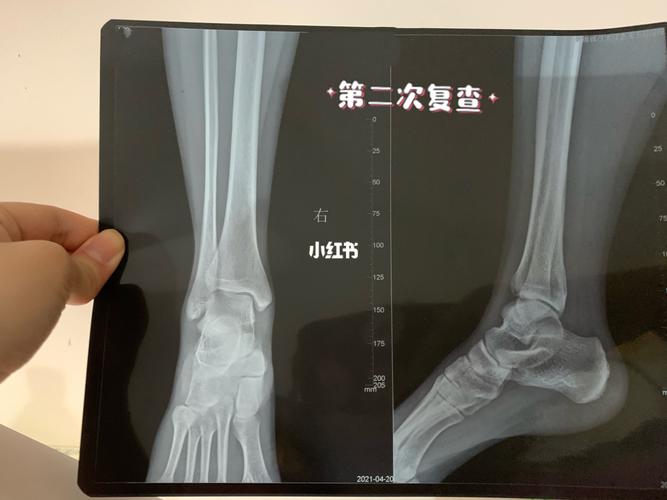

正常跟骨片子图片,骨折片子图

29岁跟骨骨折闭合撬拨复位内固定手术一例